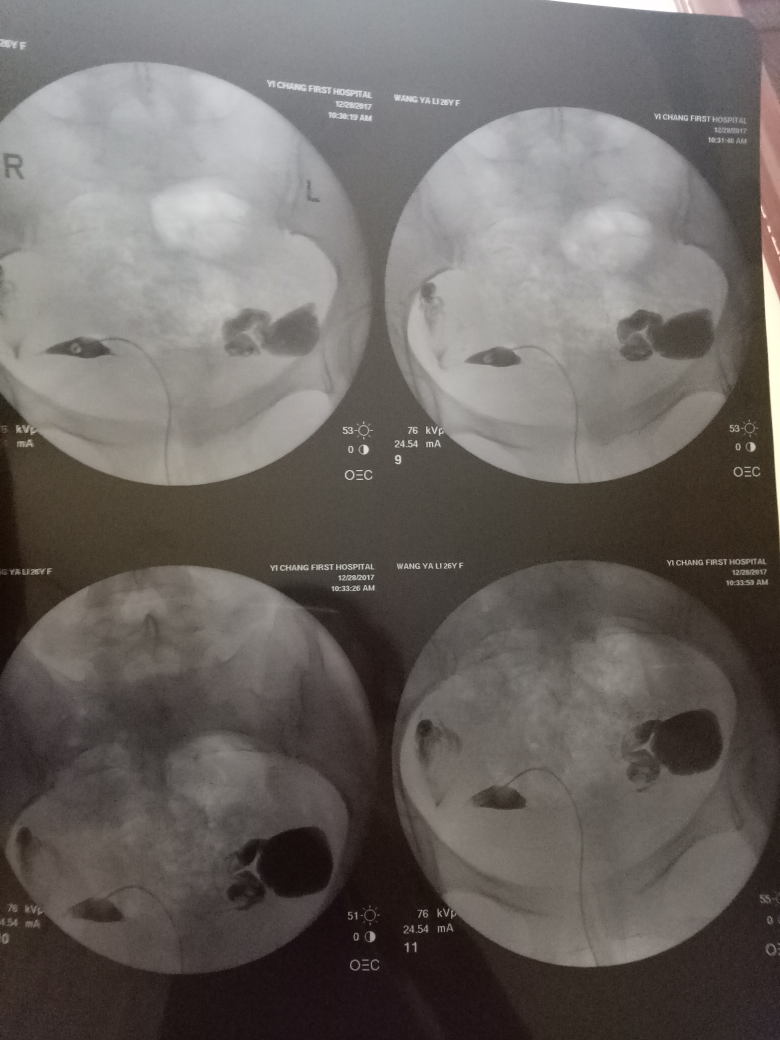

造影后第二個月懷孕的機會與準備。造影是一種醫學檢查手段,有助于了解身體內部情況。第二個月懷孕的機會取決于多種因素,如個人身體狀況、生育能力、生活方式等。在準備懷孕時,建議保持良好的生活習慣,如合理飲食、適度運動、保持心情愉悅等。還需進行必要的孕前檢查,確保身體狀況良好,為懷孕創造有利條件。造影后第二個月懷孕的機會與準備需根據個人情況而定,建議在專業醫生指導下進行。

在現代醫學中,造影技術廣泛應用于臨床診斷,對于不孕癥的診斷和治療也起到了重要作用,造影是一種通過放射線、超聲波等影像技術觀察人體內部結構和狀況的方法,完成造影后的第二個月,很多夫婦關心是否容易懷孕,造影本身并不會直接影響懷孕,但了解身體情況后,有針對性地進行治療和調理,確實有助于提高懷孕的幾率。

通過造影技術,醫生可以清晰地觀察到子宮內部環境,如子宮內膜厚度、輸卵管通暢情況等,若子宮環境良好,第二個月懷孕的機會將大大增加。

造影技術還可以評估卵巢功能,如卵泡數量、質量等,若卵巢功能正常,有助于排卵和激素分泌,從而提高懷孕幾率。